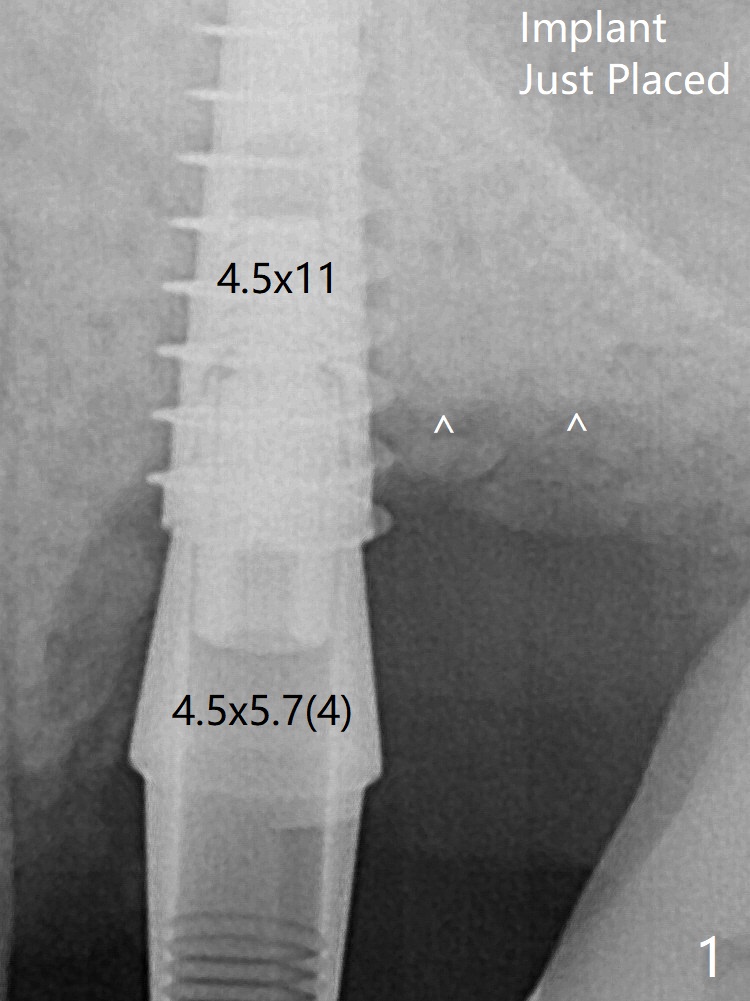

术后4个月骨粉好像覆盖远中曾经暴露螺纹(图五:^)。植体仿佛保留骨粉,促进新骨形成。